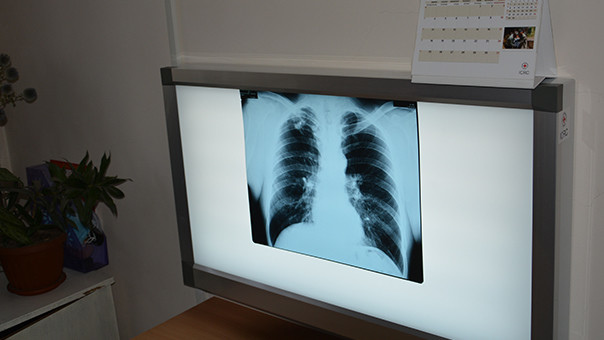

180 people die from tuberculosis in Kyrgyzstan in a year

AKIPRESS.COM - 180 people died from tuberculosis in Kyrgyzstan in 2023...